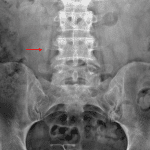

Age: 44

Sex: Female

Indication: Right-sided abdominal pain

Findings

- Calcific density measuring 8 x 4 mm projecting just below the right L4 transverse process

- Tiny calcific density overlying the lower pole of the right kidney

- Rounded calcific densities overlies the right aspect of the anatomic pelvis

- No bowel obstruction

- IUD overlies the anatomic pelvis centrally

Diagnosis

- Ureteral calculus

8 x 4 mm calcific density projecting just below the right L4 transverse process raises concern for a ureteral calculus. Consider CT for further evaluation.

Tiny calcific density overlying the lower pole of the right kidney may represent a renal calculus versus calcific debris in the fecal stream.

Rounded calcific densities overlies the right aspect of the anatomic pelvis are favored to represent phleboliths.

No bowel obstruction.